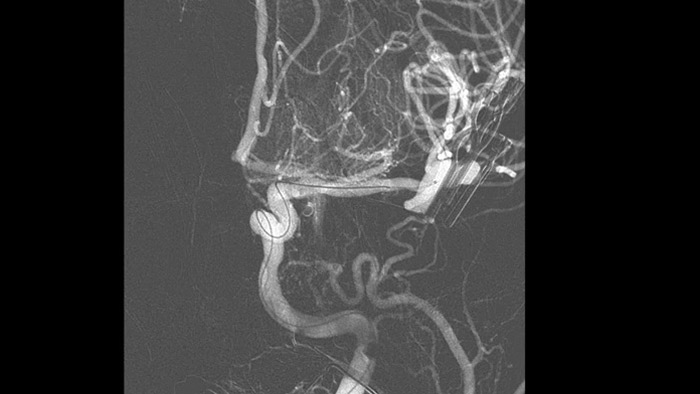

SmartCT Angio

SmartCT Angio proporciona una vista volumétrica en pocos segundos para ayudar a evaluar la ubicación, el tamaño, el cuello y la gravedad del aneurisma para la planificación del tratamiento. Los volúmenes 3D se ven con alta resolución espacial y compensación automática del movimiento del paciente.